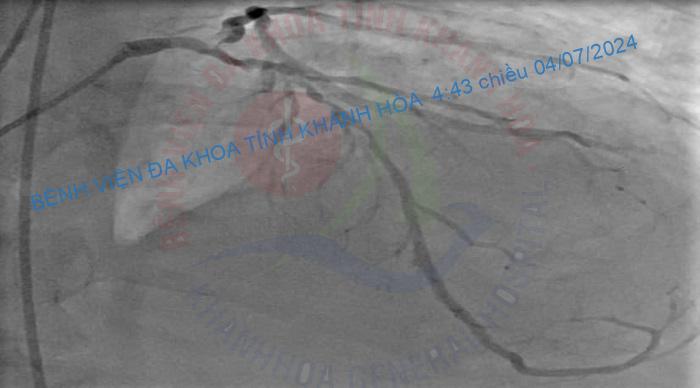

Kỹ thuật can thiệp động mạch vành qua da bằng phương pháp DK – Crush trong can thiệp tổn thương chia đôi là một kỹ thuật khó, chỉ được thực hiện ở các trung tâm tim mạch can thiệp lớn có các bác sỹ giàu kinh nghiệm. Từ hơn 3 năm nay, Khoa Tim mạch Can thiệp Bệnh viện Đa khoa tỉnh Khánh Hòa đã tiến hành kỹ thuật này một cách thường quy, có tỷ lệ thành công cao, hiệu quả và an toàn cho người bệnh./.